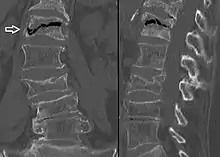

X-ray images of avascular necrosis in the early stages usually appear normal. In later stages it appears relatively more radio-opaque due to the nearby living bone becoming resorbed secondary to reactive hyperemia.[2] The necrotic bone itself does not show increased radiographic opacity, as dead bone cannot undergo bone resorption which is carried out by living osteoclasts.[2] Late radiographic signs also include a radiolucency area following the collapse of subchondral bone (crescent sign) and ringed regions of radiodensity resulting from saponification and calcification of marrow fat following medullary infarcts.

The intravertebral vacuum cleft sign (at white arrow) is a sign of avascular necrosis. Avascular necrosis of a vertebral body after a vertebral compression fracture is called Kümmel's disease.[20]